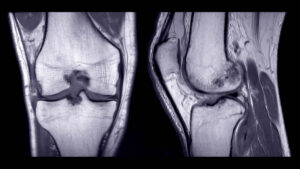

Joint conditions:

• Torn ligaments (ACL, MCL, rotator cuff)

• Torn meniscus

• Arthritis and bone spurs

• Cartilage damage

• Joint inflammation